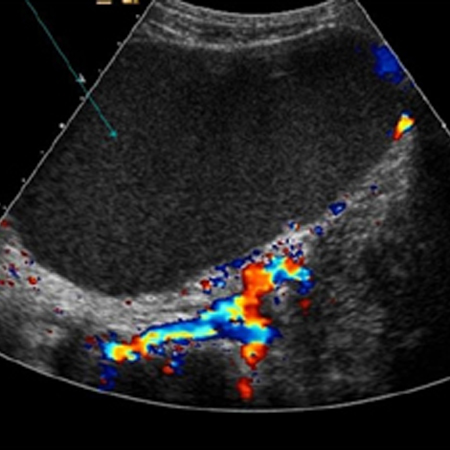

Ovarian cancer

Ovarian cyst with normal Doppler flow

From the collection of Justin C. Chura, MD, Cancer Treatment Centers of America, Philadelphia, PA